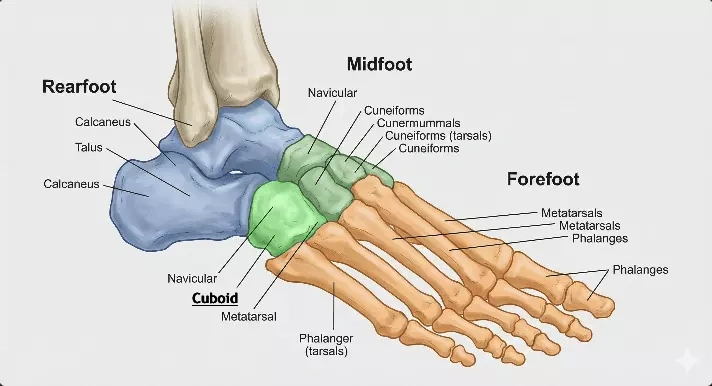

Cuboid Bone Anatomy

Location

The cuboid bone is located on the lateral (outer) side of the foot. It sits between the calcaneus (heel bone) and the bases of the fourth and fifth metatarsal bones. This position makes it an important structural link between the rearfoot and the forefoot.

Structure

As its name suggests, the cuboid bone has a roughly cube-like shape. It features multiple articular surfaces that allow it to connect smoothly with surrounding bones. These joint surfaces are covered with cartilage, enabling efficient and low-friction movement.

Articulations

The cuboid forms several important joints. Most notably, it articulates with the calcaneus at the calcaneocuboid joint, which plays a key role in foot mobility and stability. It also connects with the fourth and fifth metatarsals, contributing to the function and flexibility of the lateral column of the foot.